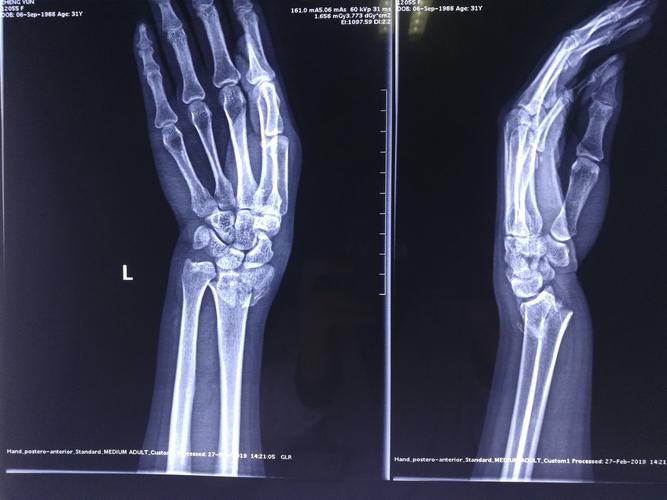

骨折接骨,跖骨骨折

厉害了车祸致多处严重骨折县医院医生微创接骨成功救治

手术演示:盖氏骨折微创钢板接骨术

手骨折

骨折x光片